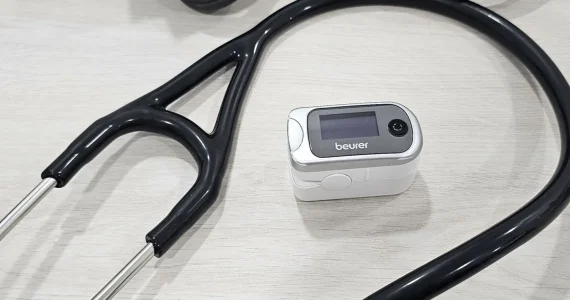

Evaluación inicial y diagnóstico clínico

Leer más sobre E.I y D.C

La valoración inicial incluye historia clínica completa, exploración física y pruebas básicas como pulsioximetría, tensiómetro y espirometría basal con broncodilatador. Estas herramientas permiten una visión clara del estado respiratorio del paciente y ayudan a orientar el diagnóstico.